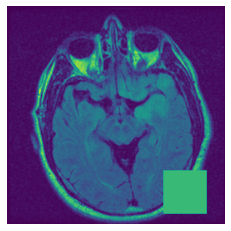

In figure 3, we present qualitative examples of different masking strategies. It is observed that, unlike context prediction and restoration, our method tends to propose targeted masks like the tumor regions or regions with abnormalities and avoids masking less helpful regions. However, it should be noted that Intelligent-Masking does not necessarily mask the tumor regions but considers all areas of interest that results in better feature learning. Examples of other masking samples are provided in supplementary materials. Furthermore, in medical images, unlike natural scenes, the structures are very local with imbalanced information throughout an image. Therefore, random masking strategies as shown in Fig 3 operate ineffectively by masking non-informative regions.

Figure 2: Qualitative examples of compared method’s strategies for masking

Figure 3: More qualitative examples of different distorting strategies including our method. We show the different self-supervised mechanisms on both datasets of MR (rows: 1-3) and ultrasound (rows: 4-6) images for lower-grade glioma and breast cancer diagnosis respectively. We include both images of normal (rows: 1,4) and cancer (rows: 2,3,5,6) conditions for each dataset. We also observe that our method treats each image based on its context information with no predetermined strategy.